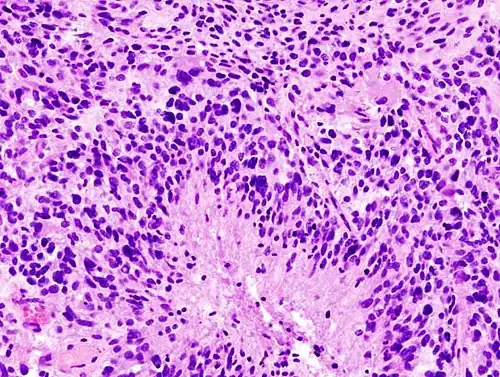

When viewed with MRI, glioblastomas often appear as ring-enhancing lesions. The appearance is not specific, however, as other lesions such as abscess, metastasis, tumefactive multiple sclerosis, and other entities may have a similar appearance.[61] Definitive diagnosis of a suspected GBM on CT or MRI requires a stereotactic biopsy or a craniotomy with tumor resection and pathologic confirmation. Because the tumor grade is based upon the most malignant portion of the tumor, biopsy or subtotal tumor resection can result in undergrading of the lesion. Imaging of tumor blood flow using perfusion MRI and measuring tumor metabolite concentration with MR spectroscopy may add diagnostic value to standard MRI in select cases by showing increased relative cerebral blood volume and increased choline peak, respectively, but pathology remains the gold standard for diagnosis and molecular characterization.

Distinguishing glioblastoma from high-grade astrocytoma is important. These tumors occur spontaneously (de novo) and have not progressed from a lower-grade glioma, as in high-grade astrocytomas.[6] Glioblastomas have a worse prognosis and different tumor biology, and may have a different response to therapy, which makes this a critical evaluation to determine patient prognosis and therapy.[45][62] Astrocytomas carry a mutation in IDH1 or IDH2, whereas this mutation is not present in glioblastoma. Thus, IDH1 and IDH2 mutations are a useful tool to distinguish glioblastomas from astrocytomas, since histopathologically they are similar and the distinction without molecular biomarkers is unreliable.[46] IDH-wildtype glioblastomas usually have lower OLIG2 expression compared with IDH-mutant lower grade astrocytomas.[63] In patients aged over 55 years with a histologically typical glioblastoma, without a pre-existing lower grade glioma, with a non-midline tumor location and with retained nuclear ATRX expression, immunohistochemical negativity for IDH1 R132H suffices for the classification as IDH-wild-type glioblastoma.[60] In all other instances of diffuse gliomas, a lack of IDH1 R132H immunopositivity should be followed by IDH1 and IDH2 DNA sequencing to detect or exclude the presence of non-canonical mutations.[60] IDH-wild-type diffuse astrocytic gliomas without microvascular proliferation or necrosis should be tested for EGFR amplification, TERT promoter mutation and a +7/–10 cytogenetic signature as molecular characteristics of IDH-wild-type glioblastomas.[60]